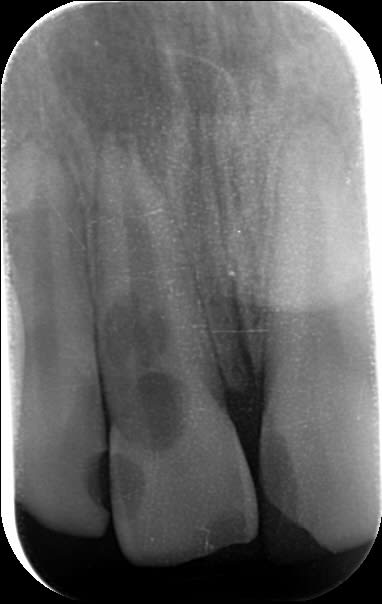

Patient âgé de 15 ans aujourd'hui, victime d'un trauma facial l'an passé avec choc sur son bloc antérieur maxillaire.

Au contrôle de mars 2015 tout semblait ok radiologiquement, les tests de vitalité étaient positifs mais pas très probants.

Je le revois hier pour vérifier tout ça et je constate à la radio une image qui pour moi est une résorption interne de la 11.Le test de vitalité est négatif.

à bien regarder la rétro, es-tu certain d'avoir une résorption interne (malgré le test de vitalité négatif)? en effet, on peut distinguer une mince couche de dentine encore radio opaque le long du canal, signe d'une résorption externe possible. Tu n'aurais pas une entrée cervicale V ou P suite à l'inflammation ligamentaire post-traumatique?

Ca ressemble plus à une résorption externe qu'interne

refait une radio légèrement décentrée

Autre cas de résorption interne, patient de 17 ans, trauma à 12 ans.

Maintenant grosse résorption interne sur 11 avec image apicale. J'ai peu d'espoir pour cette dent mais 17 ans c'est un peu jeune pour un implant amha. J'aimerais la conserver encore quelques années.

Que c'est une résorption EXTERNE.

La dent est perdue, l'objectif est de la garder jusqu'à la fin de la croissance en conservant le volume osseux qui en palatin doit être dans un sale état

J'avais réalisé l'endo en février (la radio me confirmant que c'était bien une résorption externe) et l'image à 4 mois post-endo montre une évolution très rapide de la lésion.